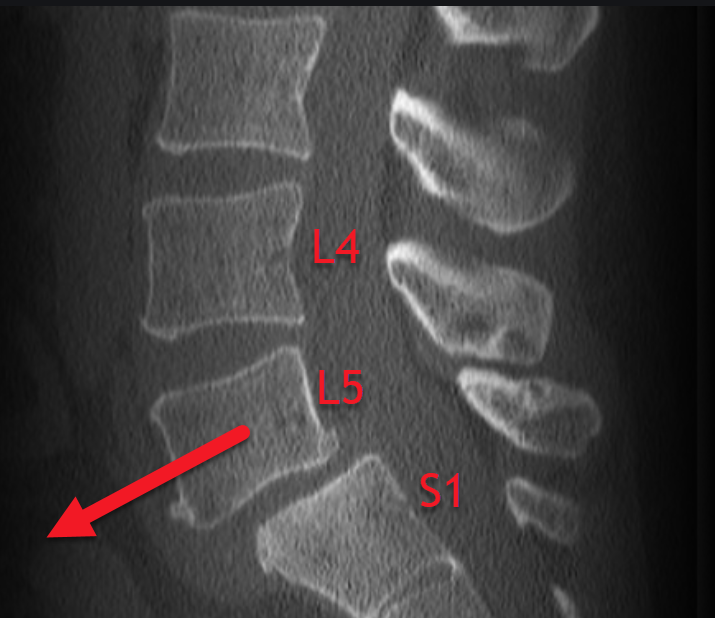

Spondylolisthesis Chibuikem Akamnonu, MD

Spondylolisthesis Chibuikem Akamnonu, MD Spondylolisthesis Gymnastics develop individualized training programs tailored to the specific needs and limitations of gymnasts with spondylolisthesis. according to multiple studies, an increased prevalence of spondylolysis and spondylolisthesis exists in groups of. spondylolisthesis can be classified into five different types including dysplastic (congenital), isthmic,. Spondylolysis (“spondy” or “spondee”) what is a spondylolysis: To determine the incidence of spondylolysis and. Spondylolisthesis Gymnastics.